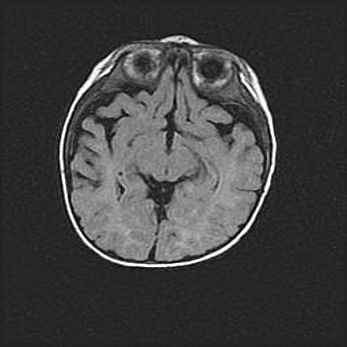

Неполная лизэнцефалия (пахигирия). Открытая гидроцефалия.

Возраст: 17 дней

Вес: 3110 г

Пол: мужской

Окружность головы: 33,5 см

Срок гестации: 35-36 недель

Лизэнцефалия—недоразвитие корковой пластинки и мозговых извилин в результате нарушения миграции нейронов коры. Поверхность мозговых полушарий гладкая. Микроскопически выявляется отсутствие нормальных слоев коры и скопление групп нейронов в подкорковом белом веществе.

Пахигирия—уменьшение числа вторичных извилин. В пораженном полушарии нервные клетки образуют толстый недифференцированный слой с неправильно расположенными нервными волокнами и группами гетеротопных клеток. Нервные клетки незрелые. Белое вещество истончено. При этом нередко аномально развит корково-спинномозговой путь.